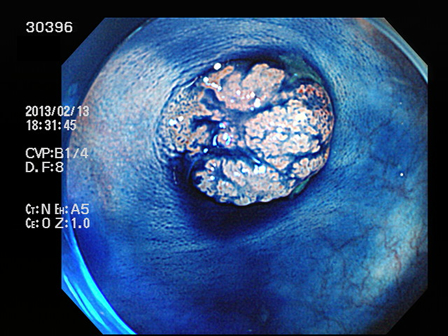

上記100名より抽出した平坦・陥凹型腺腫(=癌化の危険が高いが見落としやすい病変)の内視鏡写真

30388 30389 30391 30392 30394 30395 30396 30397 30399・・・・・・・の58名